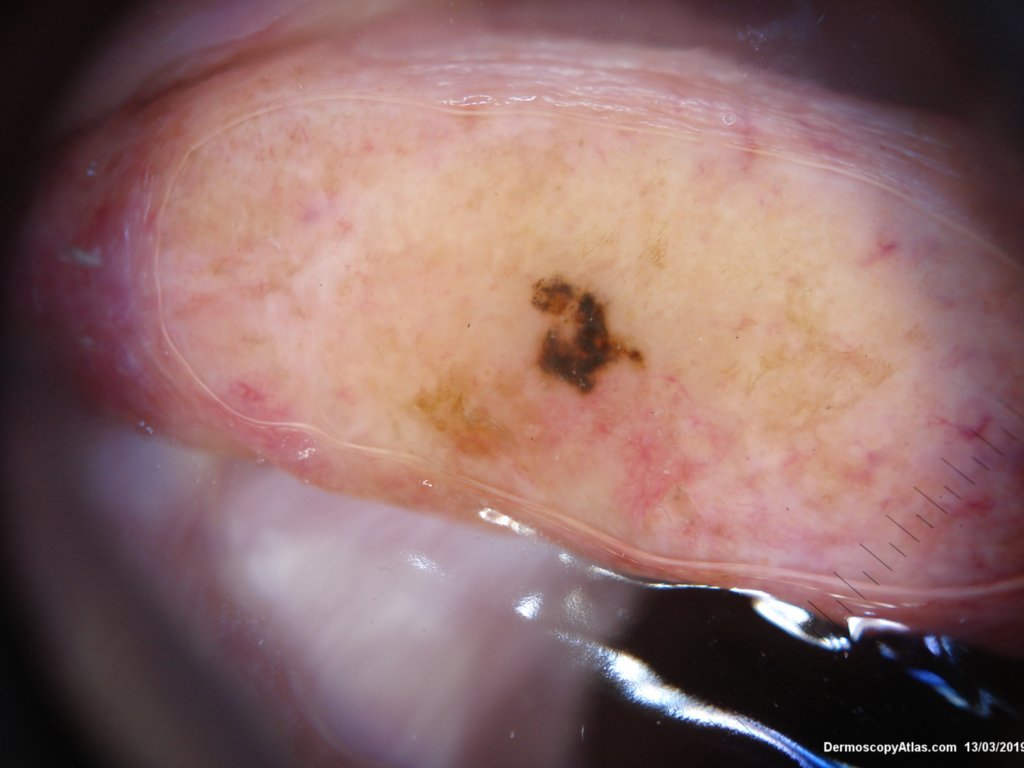

Site: Ear

Description: Pigmented lesion on pinna

This lesion was noted on the ear during a routine skin check. Patient was not aware of it. The dermatoscopy showed an irregular blue black structureless lesion with some peripheral grey dots as peppering, an excentric area of regression and some white clods.